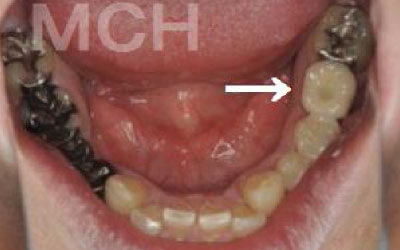

お口の状態や噛み合わせによって異なるため、一概には言えませんが、基本的には奥歯、特に一番奥とその手前の大臼歯部分がおすすめです。

噛み合わせの力の約60%以上がこの奥の二本の歯で支えられているため、ここをインプラントでしっかり治療することが非常に効果的です。